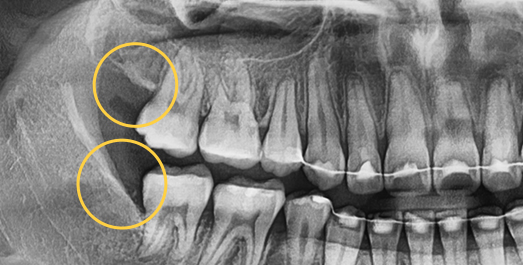

• Horizontally

impacted wisdom tooth

• Angulated

• Vertically